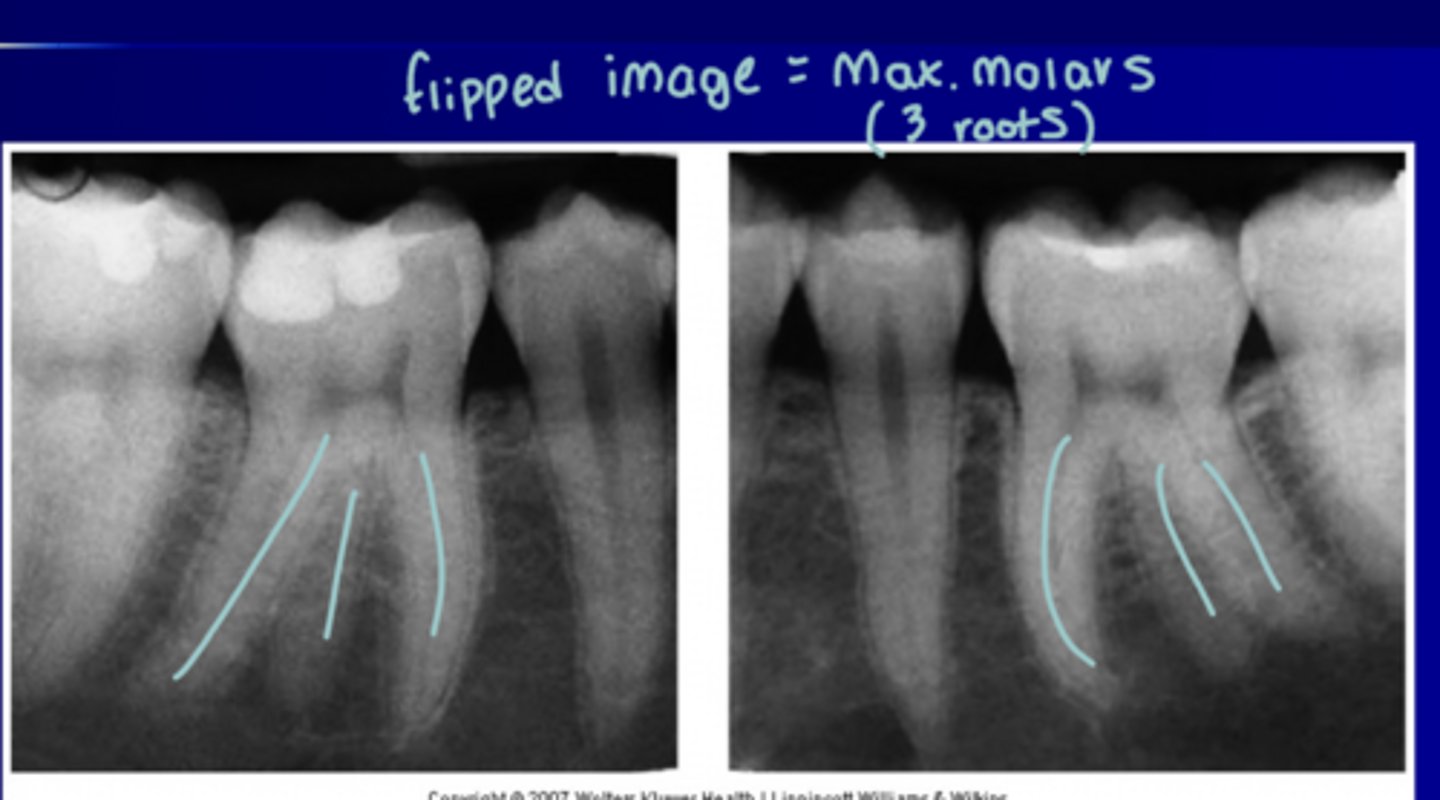

Maxillary roots on molars

3

Mandibular roots on molars

2